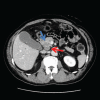

Patient concerns and diagnosis: A 66-year-old man was referred to our hospital with obstructive jaundice. Contrast-enhanced computed tomography images indicated a tumor located at the pancreatic head measuring 3.0 × 2.5 cm in diameter and invading the common bile duct. Cytological examination of the bile juice obtained by endoscopic retrograde cholangiopancreatography revealed adenocarcinoma cells. Pancreaticoduodenectomy was performed safely as radical resection.